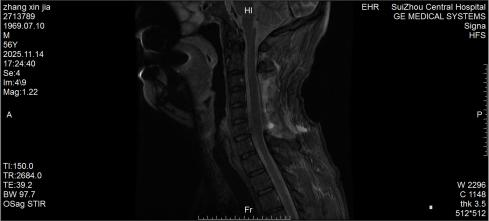

10月底的深夜,隨州市中心醫(yī)院急診醫(yī)學(xué)科來了一位特殊患者,突發(fā)劇烈頸痛伴雙手麻木,短短3小時(shí)內(nèi)肢體無力逐漸加重,連簡(jiǎn)單抬臂都難以完成。脊柱外科團(tuán)隊(duì)緊急評(píng)估后行頸椎磁共振檢查,確診為自發(fā)性頸椎椎管內(nèi)出血—— 這是今年該院救治的第5例同類患者。好在急診手術(shù)及時(shí)清除血腫、解除神經(jīng)壓迫,患者術(shù)后恢復(fù)良好,無任何后遺癥,順利出院。

圖1:術(shù)前MRI見椎管內(nèi)積血壓迫脊髓

2.確診金標(biāo)準(zhǔn):脊柱MRI能清晰顯示血腫位置和壓迫程度,是首選檢查;必要時(shí)通過DSA排查血管畸形等病因;